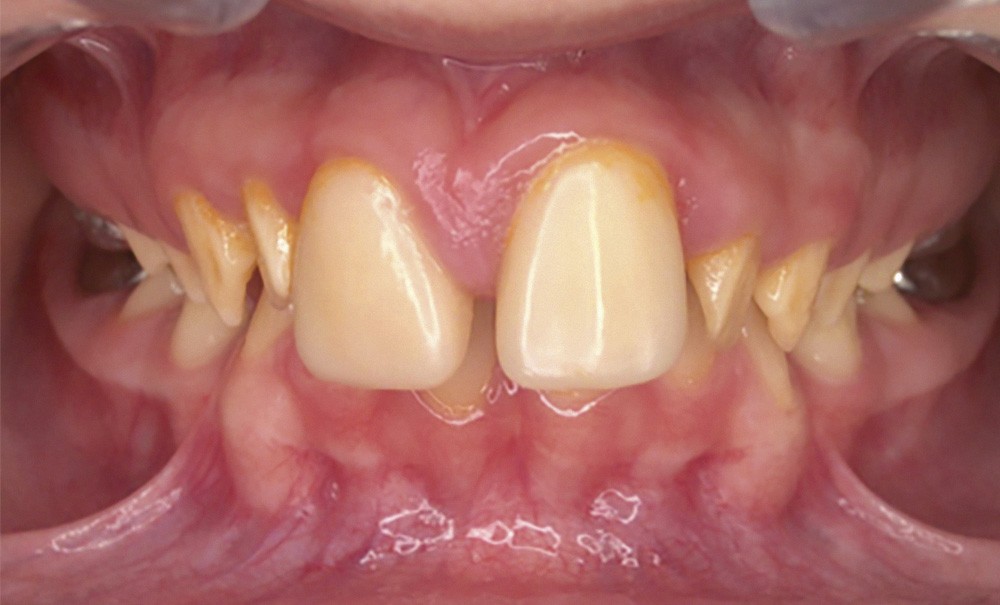

Une patiente âgée de 12 ans a été adressée au cabinet pour « une prise en charge complète sur le long terme » par son praticien traitant. Elle était accompagnée par sa mère. Elle présentait des couronnes transitoires en résine sur le secteur incisivo-canin au maxillaire ainsi que les premières prémolaires, des coiffes pédodontiques métalliques sur les premières molaires, une absence totale d’émail sur l’ensemble de la denture, à l’exclusion des bords libres des incisives mandibulaires (fig. 1 à 3). Le bloc incisivo-canin mandibulaire avait bénéficié de traitements radiculaires (fig. 4). Les incisives maxillaires présentaient des rhizalyses d’une importance significative (fig. 5 et 6). La patiente se plaignait d’hypersensibilités à la mastication et au brossage, la demande esthétique était forte.